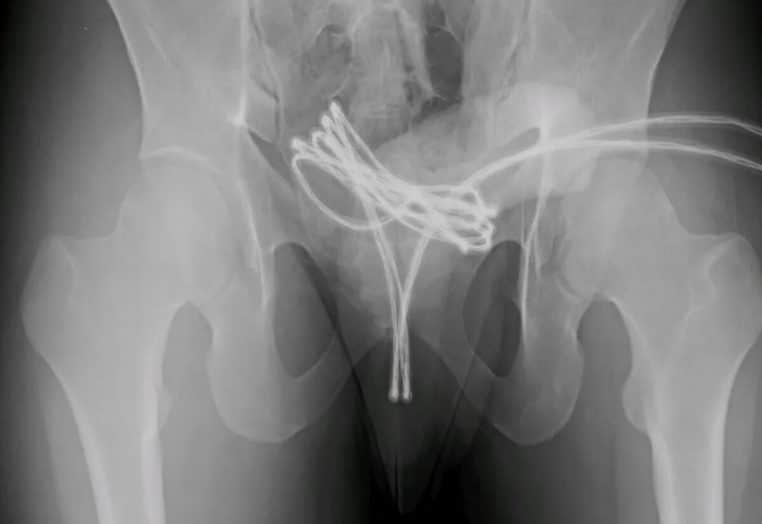

Il ne recommencera pas de sitôt. Il y a quelques jours, un étudiant américain de 21 ans a fait la Une des journaux après avoir inséré un câble USB entier dans son p*nis pour se stimuler se*uellement. Selon un rapport publié par Cureus, le jeune homme s’est rendu à l’hôpital après avoir compris qu’il ne pourrait pas retirer l’objet lui-même.

Après lui avoir fait passer un scanner, les médecins ont constaté que le câble s’était enfoncé très profondément à l’intérieur de sa vessie. Ni une ni deux, il a alors dû être opéré sous anesthésie générale. « Ils ont introduit une caméra dans son urètre afin de pouvoir le retirer avec précaution sans causer trop de dégâts », explique The Sun.